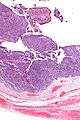

| Micrograph of transitional cell carcinoma of the ovary. H&E stain. | |

TCC of the ovary is diagnosed by examination of the tissue by a pathologist. It has a characteristic appearance under the microscope and distinctive pattern of immunostaining.[2]